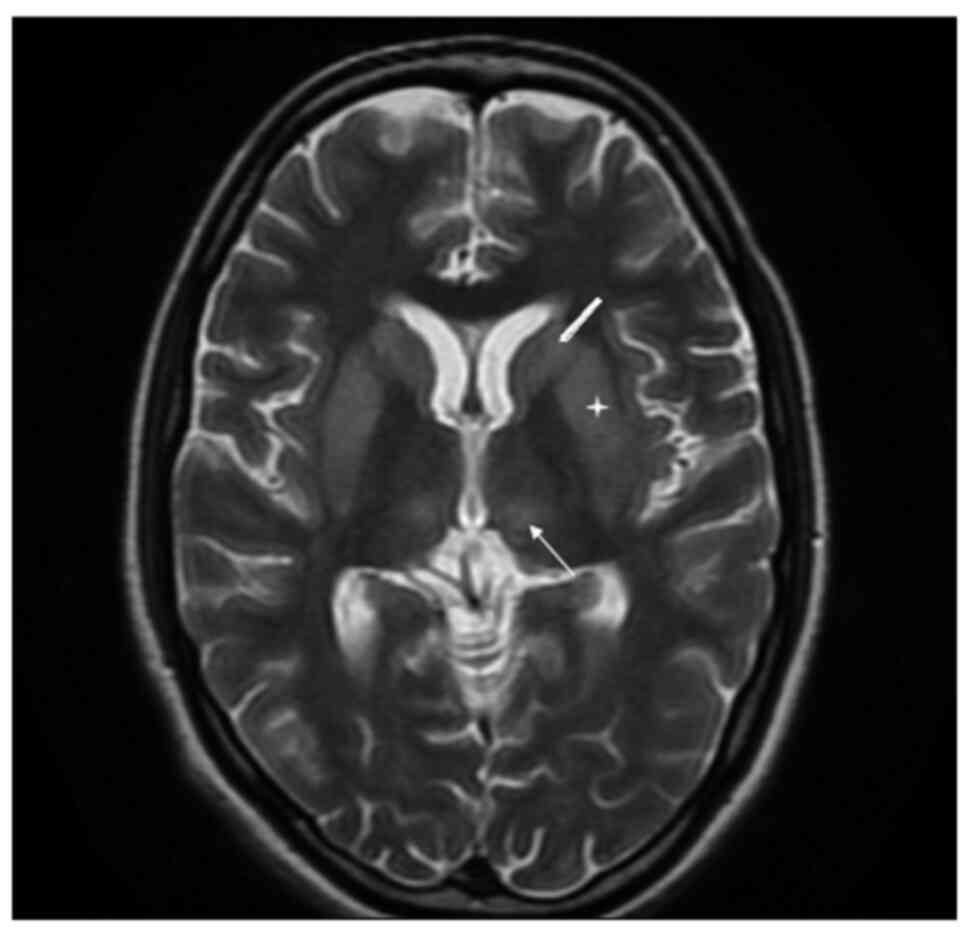

An analysis revealed that her haemoglobin level was 106 gm/l (normal range, 120-150 gm/l), the total leucocyte count was 4.1x109/l (normal range, 4-10) and her platelet count was 90,000/mm³ (range, 1.5-4.5 lakh); the differential counts were: Polymorphs, 88%; lymphocytes, 10%; eosinophils, 1%; monocytes, 1%; erythrocyte sedimentation rate, 40 mm/1st hour; random blood glucose, 4.662 mmol/l; urea, 7.14 mmol/l (normal range, 4.64-16.06 mmol/l); creatinine, 33.5 µmol/l (normal range, 35.36-106.08 µmol/l); serum sodium, 120 mmol/l (normal range, 135-155 mmol/l); serum potassium, 4 mmol/l (normal range, 3.5-5.5 mmol/l); aspartate aminotransferase, 56 IU (normal range, 5-34 IU); alanine aminotransferase, 53 IU (normal range, 6-40 IU); and alkaline phosphatase, 73 IU (normal range, 15-112 IU). Scrub and dengue serology were negative. HBsAg, hepatitis C virus and HIV serology were non-reactive. The results of a urine examination, chest X-ray and ultrasound abdomen were all within normal limits. Her arterial blood gas analysis, cerebrospinal fluid examination and electroencephalogram were within normal limits. Given her history of altered sensorium, the delayed relaxation of deep tendon reflexes, bradycardia and hyponatremia, myxedema crisis was suspected and her myxedema score was calculated. Her myxedema score was 75, suggesting myxedema crisis. Thyroid function tests revealed that T3 was <0.616 nmol/l (normal range, 1.08-3.14 nmol/l), T4 was 39.12 nmol/l (normal range, 64.35-141.57 nmol/l) and thyroid stimulating hormone (TSH) was 1.14 mIU/l (normal range, 0.550-4.780 mIU/l), suggestive of secondary hypothyroidism as opposed to sick euthyroid syndrome. Since there was a history of lactation failure, secondary amenorrhea and the delayed relaxation of deep tendon reflexes, the possibility of secondary hypothyroidism was kept. Samples for the pituitary hormonal profile were sent and management for the myxedema crisis was initiated. The patient was managed with oral levothyroxine 500 µg stat followed by 100 µg once daily through a Ryle's tube, hydrocortisone infusion, intravenous fluids, injectable antibiotics and rewarming. Her pituitary hormonal profile was suggestive of panhypopituitarism [prolactin, 76.08 pmol/l (normal range, 145.21-1,161.73 pmol/l); adrenocorticotropic hormone, 1.30 pmol/l (normal range, 1.58-13.92 pmol/l); cortisol, 108.98 nmol/l (normal range, 120.18-626.75 nmol/l); luteinising hormone, 5.4 IU/l (normal range, 1.9-12.5 IU/l); follicle stimulating hormone, 3.11 IU/l (normal range, 3.85-8.78 IU/l); and estradiol, 36.71 pmol/l (normal range, 71.58-528.62 pmol/l)]. The hormonal profile of the patient is presented in Table I. The patient exhibited an improvement in bradycardia, hypotension and hyponatremia over the ensuing 4 days; however, there was no improvement in the altered sensorium. She was awake, but not able to speak or move her limbs. A repeat neurological examination was performed, which revealed cogwheel rigidity and paraparesis. The possibility of acute parkinsonism was kept. Magnetic resonance imaging of the sella and brain was suggestive of an empty sella and extrapontine myelinolysis (Figs. 1 and 2), substantiating the diagnosis of Sheehan's syndrome with acute parkinsonism. The patient was commenced on levodopa/carbidopa following which there was a partial improvement in symptoms. She was discharged on oral hydrocortisone, levothyroxine, ethinyl estradiol and progesterone, and physiotherapy was recommended. At the 6th month of follow-up, the patient was communicating well, the paraparesis had improved and she could perform all household activities.

Figure 1

Magnetic resonance imaging of the brain (axial view; T2W) illustrating hyperintensity in bilateral caudate nuclei (thick arrow), putamen (asterisk) and thalamus (thin arrow).